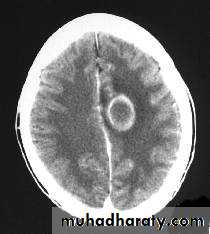

CT finding

Hypo dense area surrounded by large area of peri focal edema, which may cause shifting of the midline).

After injection the lesion show ring pattern of enhancement so the peripheral aspect of the lesion become clearer.

DDx

Secondary metastasis, patient have history of primary malignancy, beside absence of the fever.

Primary necrotic tumor, neither Hx of primary, nor fever are present.